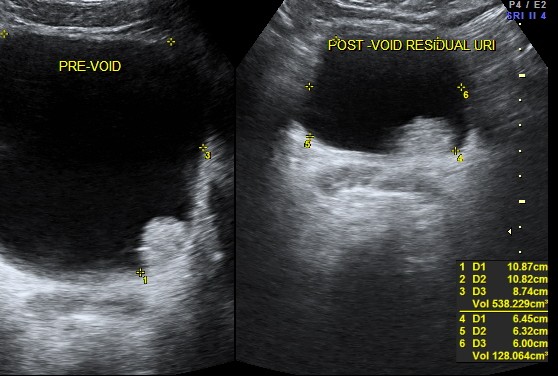

the last case was vesical calculi ; this one was a urinary bladder carcinoma .

47 year old man presented with complaints of painless hematuria ; he had a similar self limiting episode 3 months ago , which he ignored.His ultrasound pictures are given below

the next is a post void picture showing the mass

this patient underwent surgery and histopathology proved the diagnosis of bladder carcinoma and he is doing well now.